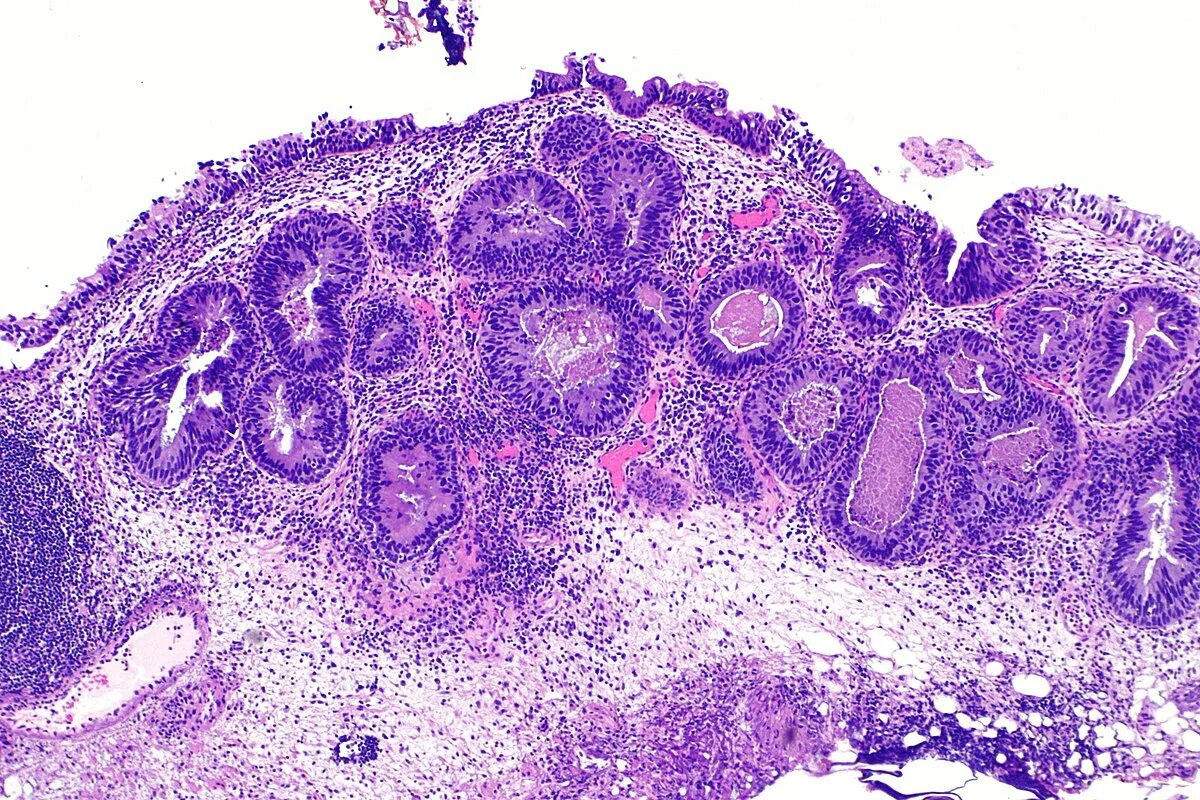

Высокодифференцированная аденокарцинома кишки